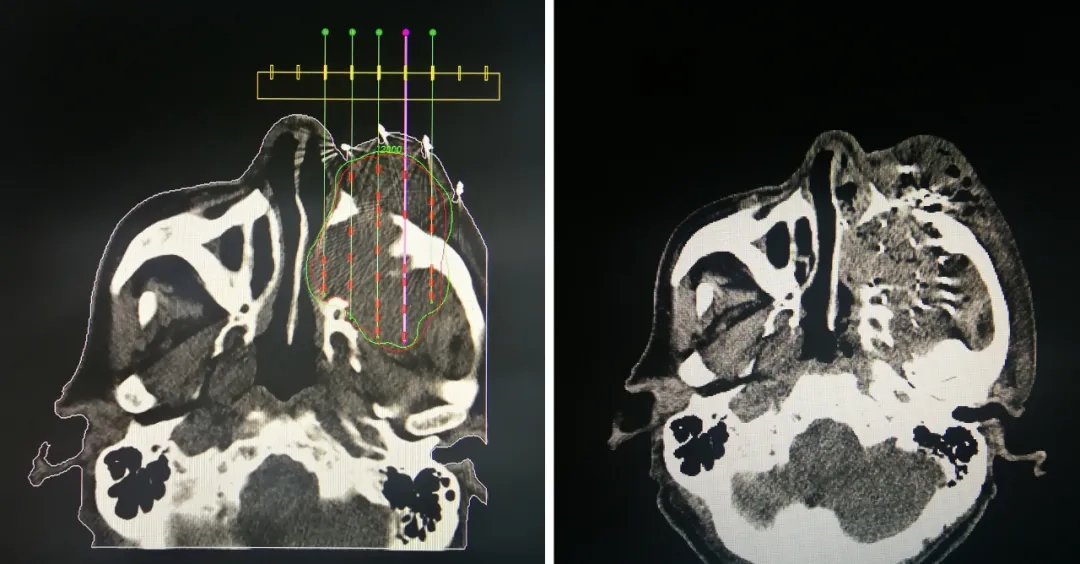

我院采用125-碘粒子植入技术治疗上颌窦肿瘤

125-碘粒子植入治疗肿瘤技术,是指通过超声、CT等影像引导技术将核素125-碘粒子直接植入到肿瘤瘤体内部或瘤体周围的技术。

125-碘粒子,其半衰期为59.6天,粒子平均能量30KeV,粒子在肿瘤内部持续放射出低能量γ射线。植入瘤体内的125-碘粒子,近距离照射肿瘤组织,分别在1.7cm范围内最大限度杀灭肿瘤细胞,能迅速杀死肿瘤细胞,截断肿瘤细胞扩散的途径,对正常组织无伤害,从而达到治疗目的。125-碘粒子植入治疗肿瘤,缩小瘤体、缓解局部症状效果明显,特别是对年龄偏大、无法手术、肿瘤放化疗效果不佳的患者更是一种新的治疗选择。

病例详情:

患者,男,81岁,2019年12月,发现左侧颜面部肿大伴疼痛,左侧颜面局部肿的包块进行性增大并疼痛感加重,左侧眼球眼球外突。2020年2月在某医院行头颅CT检查,诊断为上颌窦肿瘤。于2020-07-27入住运城同德医院,入院后与2020年8月3日采用125-碘粒子植入治疗技术治疗。粒子植入术前做TPS计划,术中植入手术顺利、成功、患者无不适感觉,术后进行TPS计划符合率验证。2020年11月8日(术后3个月)来院复诊,患者左侧颜面部肿块消失、外突的眼球回缩至“正常”,患者的左侧颜面部的肿胀、疼痛等不适感觉消失。整体治疗效果明显。

125-碘粒子植入治疗技术先进,对肿瘤局部作用均匀、疗效好、副作用少。125-碘粒子针对肿瘤点对点治疗,定位更准确、局部治疗效果更明显。125-碘粒子具有“无刀手术”效果,对周围正常组织损伤极小,术后2-3天即可出院。